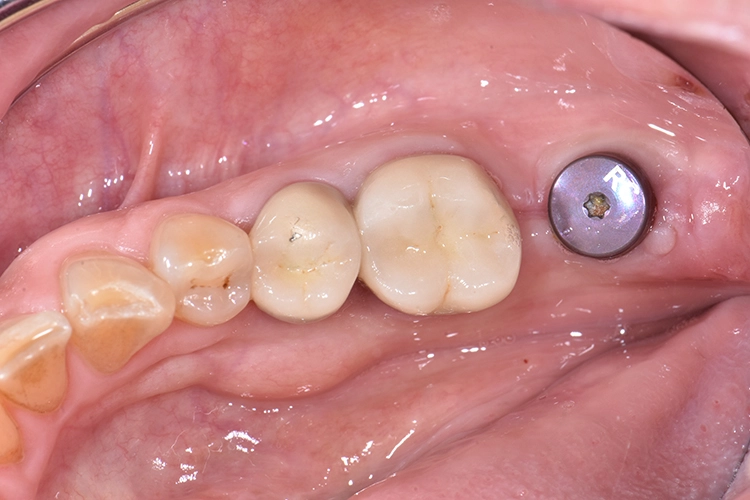

Bilder: Dr. Lampson / HannkerDie Kronen für die Zähne 45 und 46 wurden mit einem selbstadhäsiven Befestigungs-Composite (G-CEM LinkAce; GC*) auf den Pfeilerzähnen angebracht, die Krone für Zahn 47 auf das Implantat geschraubt (35 Ncm) und der Zugang im unteren Bereich mit Teflon, im oberen mit Composite gefüllt (Abb. 19). Nach Überprüfung der Okklusion wurde der Patientin das Endergebnis präsentiert.